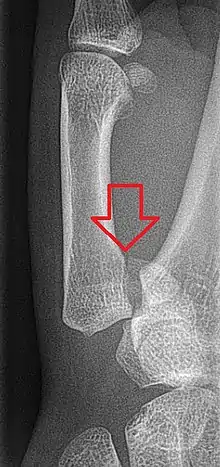

Bennett fracture is a type of partial broken finger involving the base of the thumb, and extends into the carpometacarpal (CMC) joint.[1]

This intra-articular fracture is the most common type of fracture of the thumb, and is nearly always accompanied by some degree of subluxation or frank dislocation of the carpometacarpal joint.

In the case of the Bennett fracture, the proximal metacarpal fragment remains attached to the anterior oblique ligament, which in turn is attached to the tubercle of the trapezium bone of the CMC joint. This ligamentous attachment ensures that the proximal fragment remains in its correct anatomical position.

The distal fragment of the first metacarpal bone possesses the majority of the articular surface of the first CMC joint. Unlike the proximal fracture fragment, strong ligaments and muscle tendons of the hand tend to pull this fragment out of its correct anatomical position.